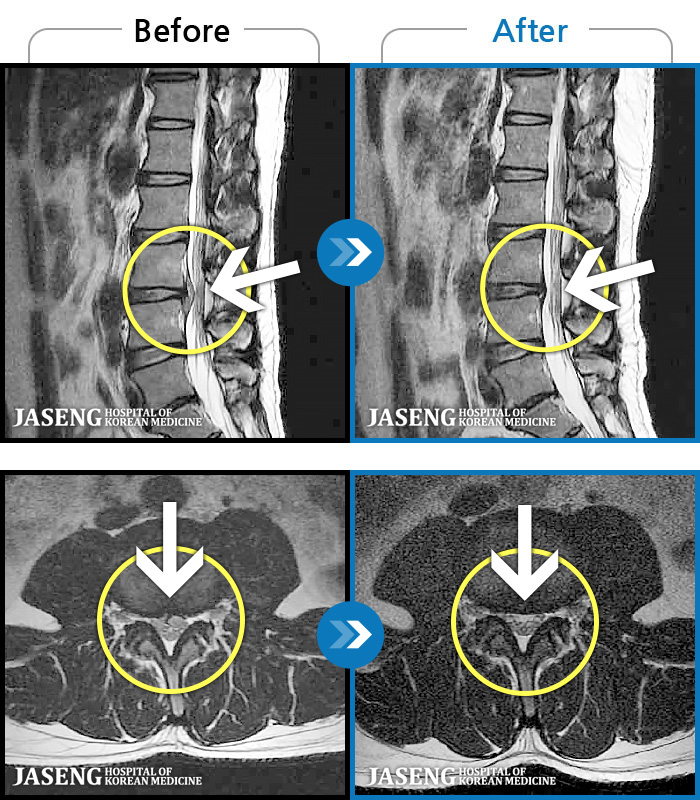

허리디스크

보라매 · 빈상은 원장

엉치에서 좌측 다리까지 통증, 저림으로 움직일 수가 없어요.

촬영시기

2024.08.03 ~ 2025.05.02

2025.12.12

조회수 68